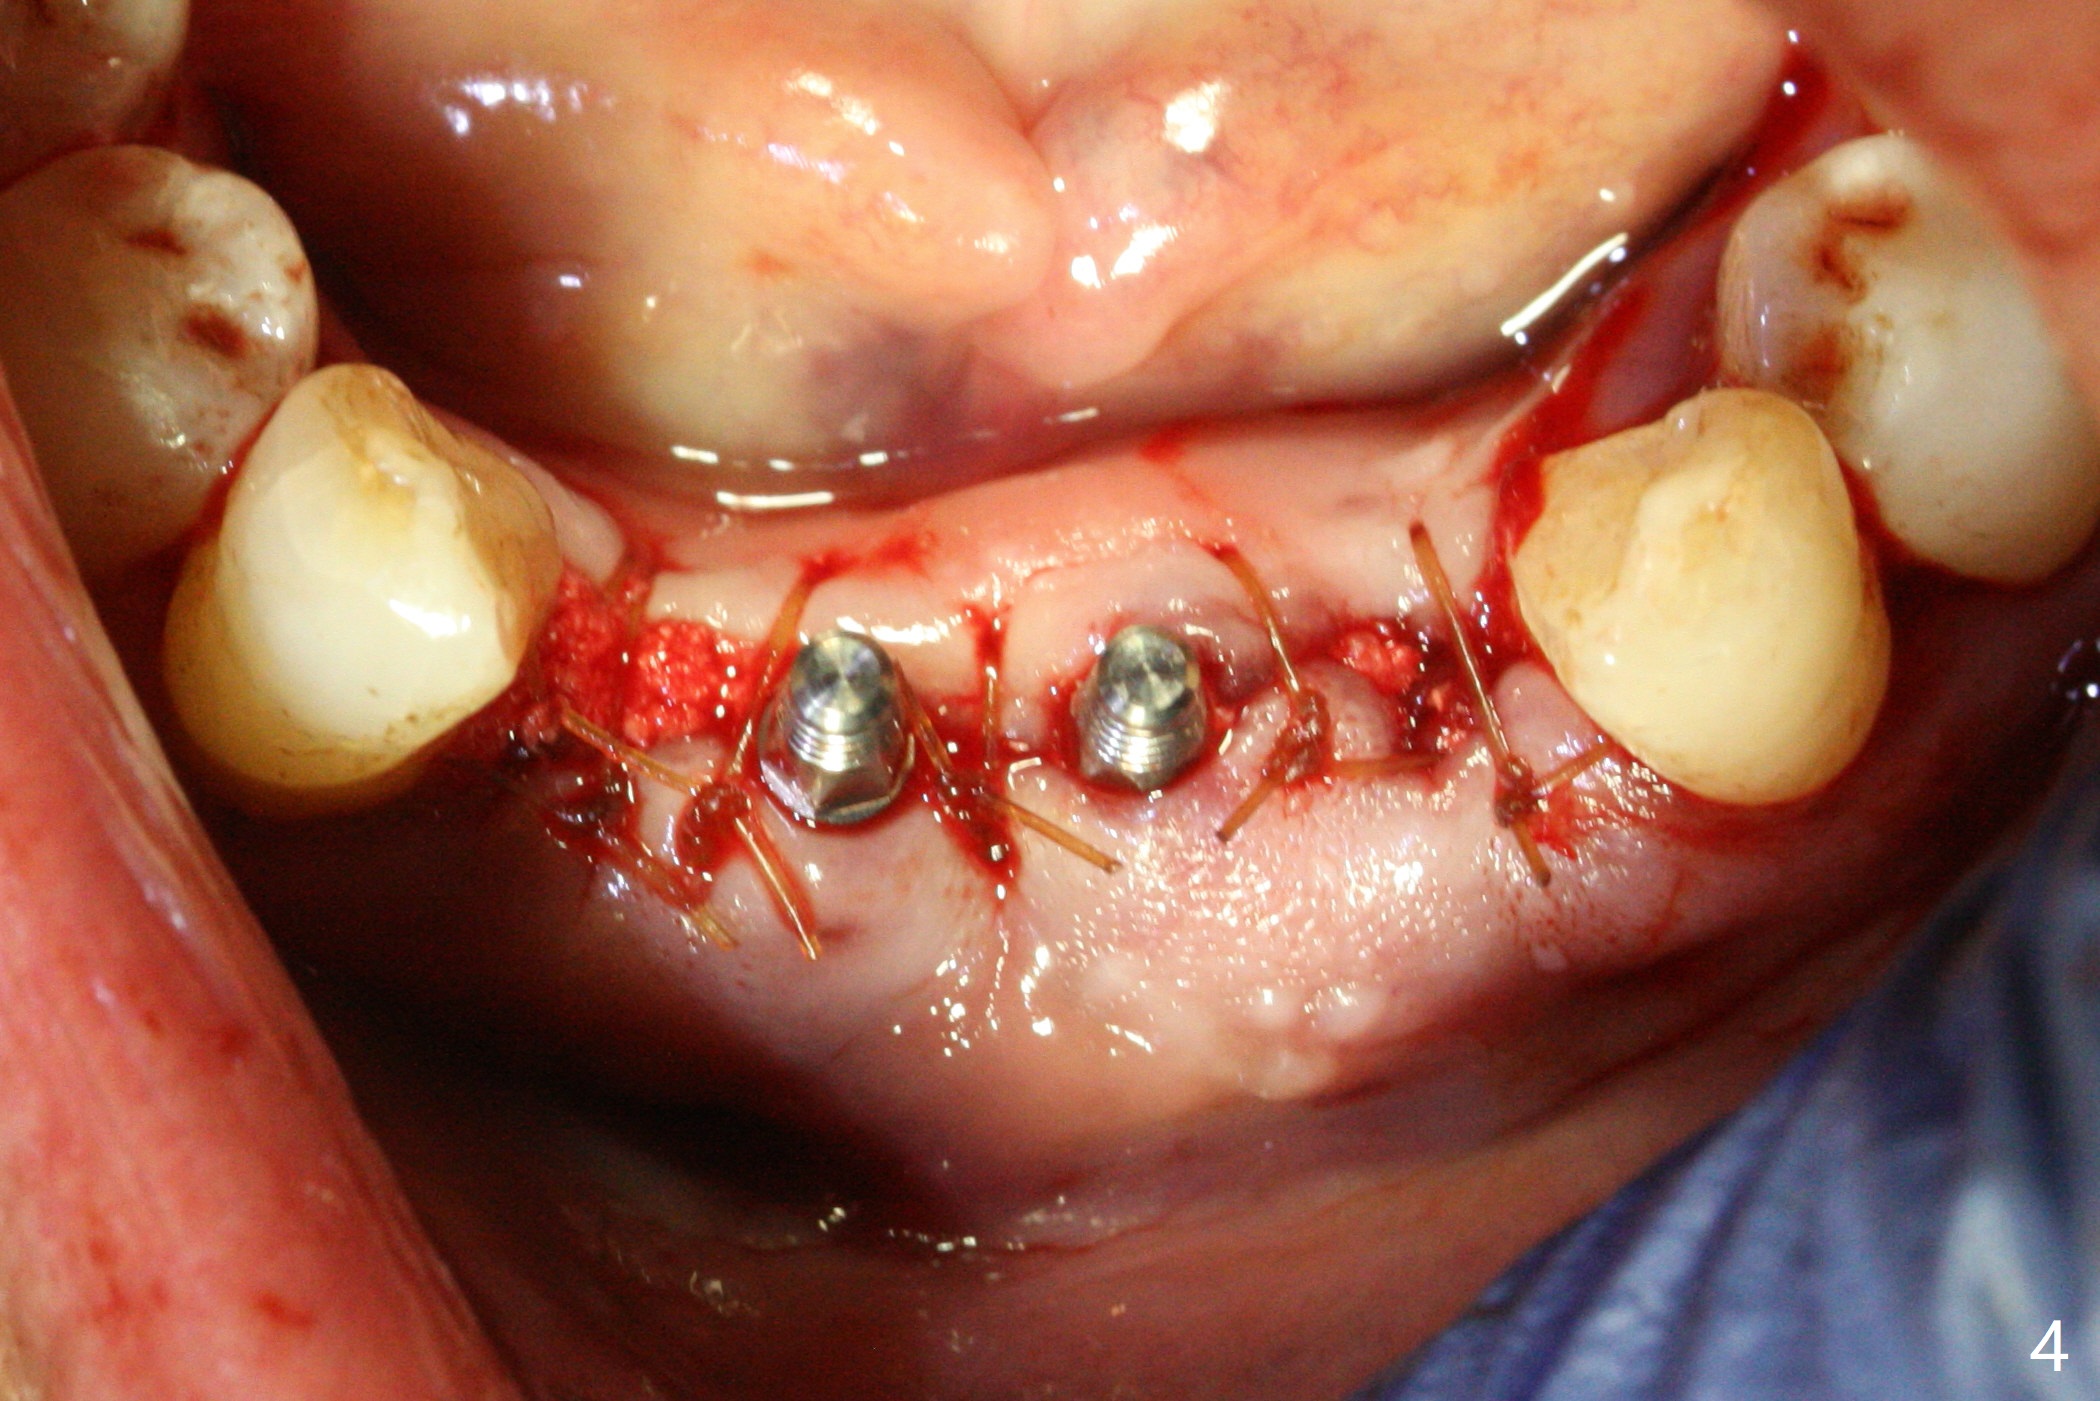

When the patient (smoker) returns for treatment, the apical abscess associated with #25 and 26 reduces with oral Amoxicillin. He agrees with 4 incisor extraction because of 2 apical fistulae (Fig.1 >). Osteotomy starts at the central incisor sockets due to mesial root exposure of the canines (Fig.2 arrowheads) and buccal alveolar bone fracture between #23 and 24 (Fig.7). Two of 3x14(4) mm 1-piece implants are placed with ~ 2 mm buccal gap (Fig.3). After Vanilla graft is placed in the bony defects (Fig.5 *) and Osteogen plug, sutures are placed (Fig.4). The implants are then placed deep to decrease thread exposure (Fig.6). Periodontal dressing is applied instead of provisional. Alveolar bone fracture between #23 and #24 accounts for why an implant is less suitably placed at #24 (Fig.7). Three months postop, composite is added to the pontic areas of the provisional (Fig.8 *). When the provisional is seated, the convex pontics press the used-to-be-flat gingiva (Fig.9 arrows). Thus the concave gingiva forms (Fig.10 *) with corresponding papillae (^). In fact the photos of Fig.8-10 is taken ~3 weeks later. Most of the grafted bone remains in place 3.5 months postop (Fig.11). A piece of floss with 2 knots in one end is placed between the middle units of the final bridge before cementation (Fig.12 (4 months 10 days postop)). In fact removal of residual cement is not so simple. It is tedious (Fig.13,14). An asymptomatic buccal fenetration with implant thread exposure is found 2 months post cementation and persists for another month in spite of advice to reduce smoking (1/2 ppd) and use of water pik (Fig.15). The area will be debrided, followed by bone graft and PRF in a month.